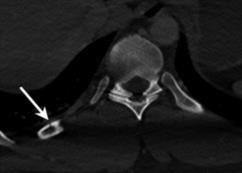

Rib fractures are a common and potentially severe injury that can be challenging and labor-intensive to detect in CT scans. While there have been efforts to address this field, the lack of large-scale annotated datasets and evaluation benchmarks has hindered the development and validation of deep learning algorithms. To address this issue, the RibFrac Challenge was introduced, providing a benchmark dataset of over 5,000 rib fractures from 660 CT scans, with voxel-level instance mask annotations and diagnosis labels for four clinical categories (buckle, nondisplaced, displaced, or segmental). The challenge includes two tracks: a detection (instance segmentation) track evaluated by an FROC-style metric and a classification track evaluated by an F1-style metric. During the MICCAI 2020 challenge period, 243 results were evaluated, and seven teams were invited to participate in the challenge summary. The analysis revealed that several top rib fracture detection solutions achieved performance comparable or even better than human experts. Nevertheless, the current rib fracture classification solutions are hardly clinically applicable, which can be an interesting area in the future. As an active benchmark and research resource, the data and online evaluation of the RibFrac Challenge are available at the challenge website. As an independent contribution, we have also extended our previous internal baseline by incorporating recent advancements in large-scale pretrained networks and point-based rib segmentation techniques. The resulting FracNet+ demonstrates competitive performance in rib fracture detection, which lays a foundation for further research and development in AI-assisted rib fracture detection and diagnosis.